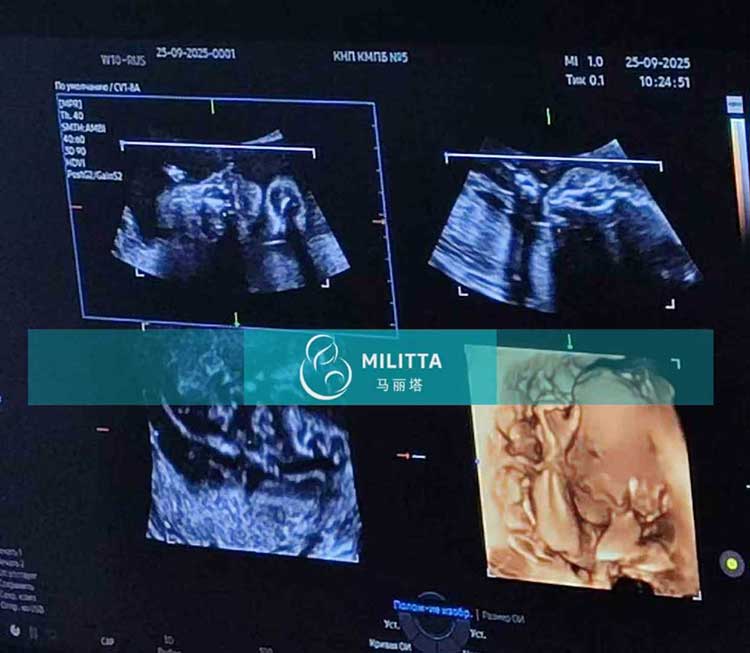

陪同两位在乌克兰LITA丽塔医院移植胚胎的试管妈妈在基辅做孕23周四维彩超,孕32周+B超,检查胎儿身体各种指标都发育都很好,感谢试管妈妈的耐心照料~